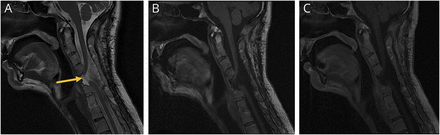

一个48岁的男子提出广义疼痛恶化。他有一个复杂的历史颈椎畸形和C2-T4前部和后部检测融合。在神经系统检查、颅神经、感觉和力量都完好无损。影像表现突出的脊髓的corpectomy缺陷和脊髓软化椎间盘髓索(图)。组件的病人的痛苦是由于脊髓软化。脊髓疝(原理图),医源性时,主要发生在后路的设置和相关pseudomeningocele形成。原理图也可以开发颈椎前路减压和潜在的并发症硬脑膜的缺陷是最可能的机制。1,2

MRI显示脊髓疝入C5 corpectomy缺陷(一个矢状t2加权图像[B]矢状t1加权图像没有对比,[C]矢状t1加权图像对比)。矢状核磁共振造影显示腰椎间盘突出脊髓前方的C5 corpectomy缺陷。有明显变薄的颈线在这个级别异常T2 hyperintensity,兼容脊髓软化(箭头)。Precontrast和postcontrast t1影像不展示任何异常增强。